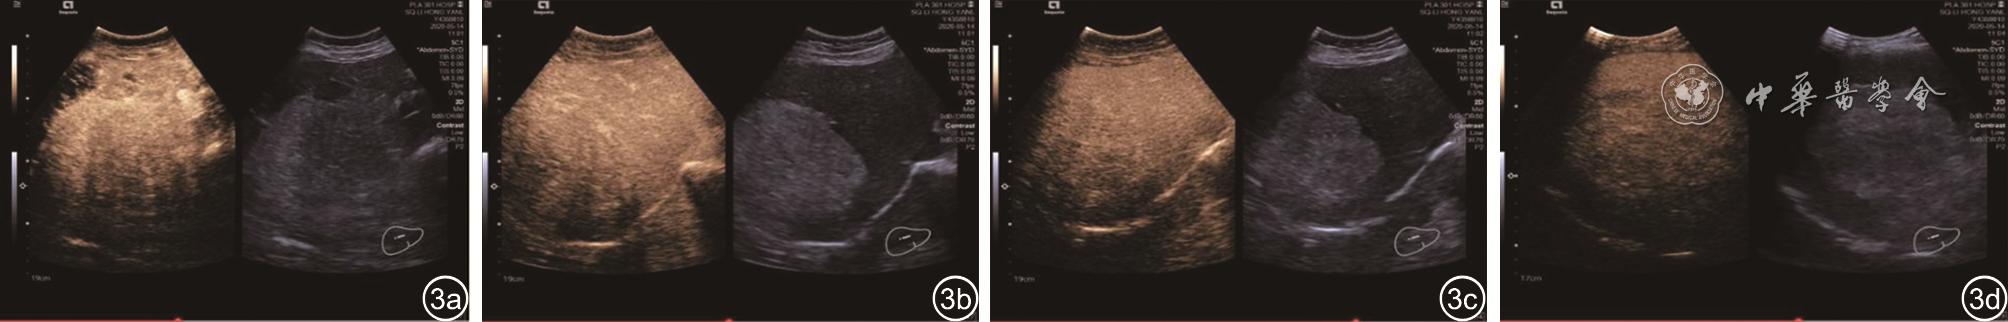

图1 肝右叶高回声肿块MRI图像。图a为T1正相位表现为高信号;图b为T1反相位病灶内信号明显减低,病灶周边可见勾边效应;图c为T2非抑脂相呈稍高信号;图d为T2抑脂相信号明显减低;图e为T1相增强动脉期病灶呈高低混杂信号,以稍低信号为主;图f为T1相增强门静脉期病灶呈进行性不均匀强化